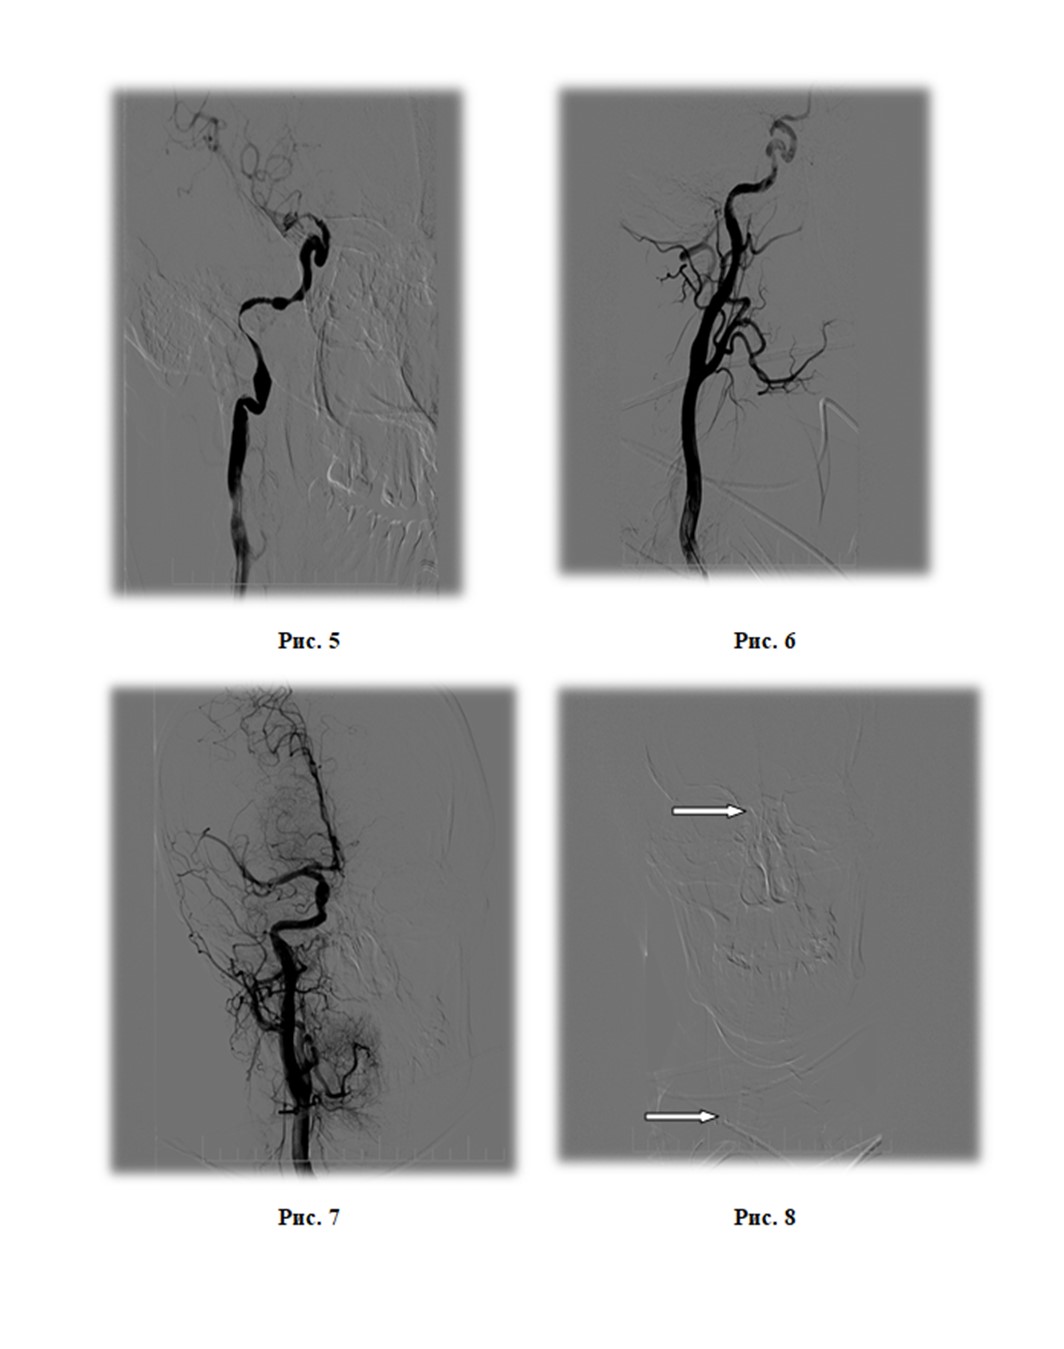

В 14:00 выполнена церебральная ангиография. Диагностирована окклюзия ПВСА в первом сегменте (симптом «пламени свечи»), в остальных артериях головного мозга - без видимых стенозов и окклюзий. Из левой ВСА через переднею соединительную артерию контрастируется правая передняя мозговая артерия (рис. 1, рис. 2). Учитывая молодой возраст пациентки и неотягощенный анамнез, а так же отсутствие поражений в других сосудистых бассейнах головного мозга была заподозрена спонтанная диссекция ПВСА. Коллегиально принято решение о выполнении механической тромбоэкстракции из ПВСА. Через проводниковый интродюссер 7F с применением проводникового катетера 6F с баллоном на конце для защиты от дистальной эмболии, выполнена реканализация ВСА до интракраниального отдела, дальше проводник завести не удалось. Выполнена тромбоэктракция стент-ретривером Solitaire FR с зоны сифона, получены фрагменты красного тромба. При последующем контрастировании ПВСА визуализирована до уровня сегмента C6, дистальнее оставалась окклюзирована. (рис. 3). Повторно проведена реканализация ВСА, микропроводник на микрокатетере заведен в правую среднюю мозговую артерию (ПСМА), после чего последовательно выполнены четыре тракции Solitaire FR из ПСМА с удалением множества красных тромбов максимальным размером до 5 мм. При контрольном контрастировании кровоток по ПВСА и ПСМА восстановлен, но имеется винтовая диссекция ВСА (симптом «четок») не доходящая до зоны интракраниального отдела (рис. 4, рис. 5). Диссекция лимитирует кровоток и стенозирует просвет артерии до 95%. При контрастировании через 5 минут признаки редукции кровотока. Для препятствия ретромбозу в ПВСА принято решение о стентировании артерии. Учитывая анатомические особенности, протяженность диссекции, а так же соответствие расходного материала принято решение о установке стента с доставкой под проводник диаметром 0,035", размером 6,0 х 150 мм. С техническими трудностями выполнена имплантация самораскрывающегося нитинолового стента от зоны сифона ПВСА до уровня средней трети правой общей сонной артерии (рис. 6, рис. 7, рис. 8). При контрольном контрастировании – раскрытие стента удовлетворительное, кровоток восстановлен и соответствует mTICI-3.